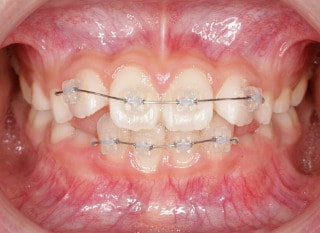

小児期の第二段階

治療中